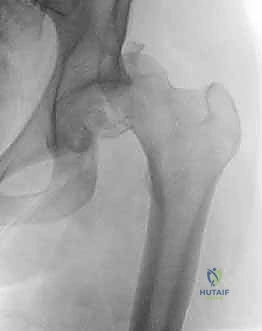

- الأشعة السينية العادية (X-Rays): يتم أخذ صور أمامية خلفية (AP View) للحوض والورك. غالباً ما تُظهر الأشعة الخلع بوضوح، لكنها قد لا تُظهر تفاصيل كسر رأس الفخذ بدقة بسبب تراكب العظام.

- الأشعة المقطعية المحوسبة (CT Scan) ثلاثية الأبعاد: هي المعيار الذهبي (Gold Standard) وأداة لا غنى عنها في تشخيص كسور رأس الفخذ. يصر الدكتور هطيف على إجراء أشعة مقطعية بشرائح رقيقة (Fine cuts) وإعادة بناء ثلاثي الأبعاد (3D Reconstruction). هذه الأشعة تحدد:

- حجم وموقع القطعة المكسورة من رأس الفخذ.

- وجود أي شظايا عظمية صغيرة (Loose bodies) داخل المفصل تعيق الرد.

- حالة التجويف الحقي وما إذا كان هناك كسر مصاحب فيه.